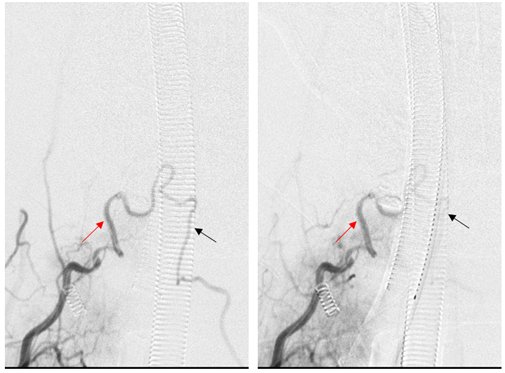

右斜位,右侧甲状颈干造影动脉期,显示颈升动脉(红箭)供应颈4-5水平瘘口(黑箭),静脉迅速出现,伴静脉球形成(白箭)。

栓塞后复查右侧甲状颈干造影见引流静脉不显影,瘘口完全栓塞。右侧颈升动脉(红箭)经吻合处逆流进入左侧颈升动脉(黑箭)。证实双侧颈升动脉供应相同瘘口。